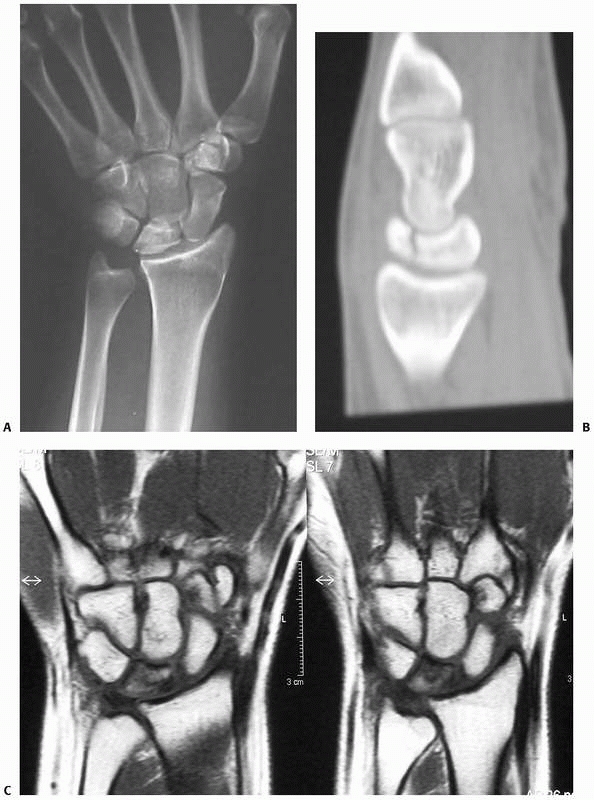

![]() |

FIGURE 29-16 A. The MRI scan demonstrates a clear fracture line of the scaphoid (proximal pole). B. It is difficult to identify the proximal fracture by native radiographs.

fractures (Fig. 29-16).27,65

FIGURE 29-15

An occult fracture was detected 10 days after a fall on the outstretched hand. This fracture was not visible on the initial set of radiographs |